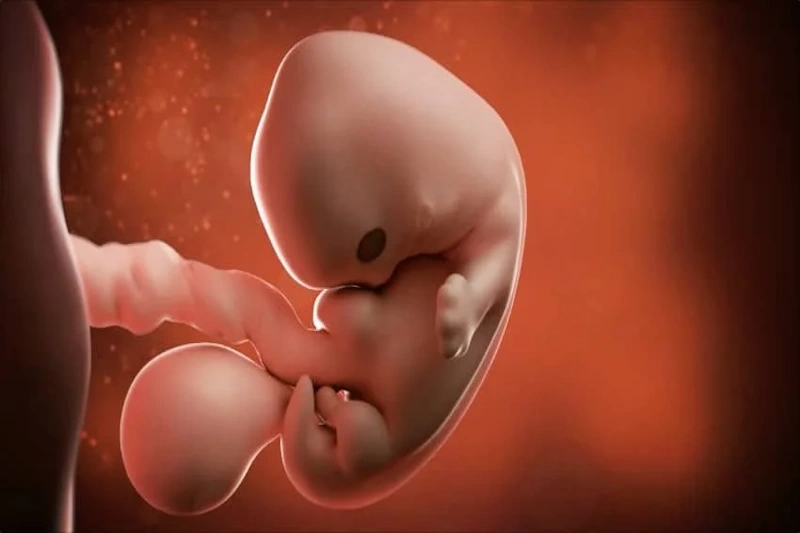

Ҳарчанд кӯдак танҳо тақрибан 3 см дарозӣ дорад ва то ҳол мисли спирал печидааст, он босуръат меафзояд. Аксари афзоиш дар майна рӯй медиҳад, ки дар он тақрибан 100,000 ҳуҷайраи асабӣ нав дар як дақиқа ташаккул меёбанд.

Ин ҳуҷайраҳо паҳн мешаванд ва пайваст мешаванд, то роҳҳои ибтидоии системаи асаби марказиро ташкил кунанд. Ҳангоми таваллуди кӯдак, майнаи ӯ зиёда аз 10 миллион ҳуҷайраи асабии пайвастшударо хоҳад дошт.

Теъдоди зарбаҳои дил аз ҳафтаи 6 тезтар аст ва дар қубури дил сутунчаҳои хурд ба вуҷуд меоянд. Ҳуҷайраҳо босуръат тақсим мешаванд, то ба 40 ҷуфт мушак ва 23 ҷуфт сутунмӯҳра дар сутунмӯҳра табдил ёбанд. Шохаҳои даст ва пой ба зудӣ меафзоянд ва акнун ба парҳои хурд монанданд. Гӯшҳои берунии кӯдак тадриҷан ташаккул меёбанд ва банақшагирии буғумҳо дар оринҷ, китф ва зонуҳо низ вуҷуд дорад. Тақрибан ташаккули пӯстҳои чашм анҷом ёфтааст.